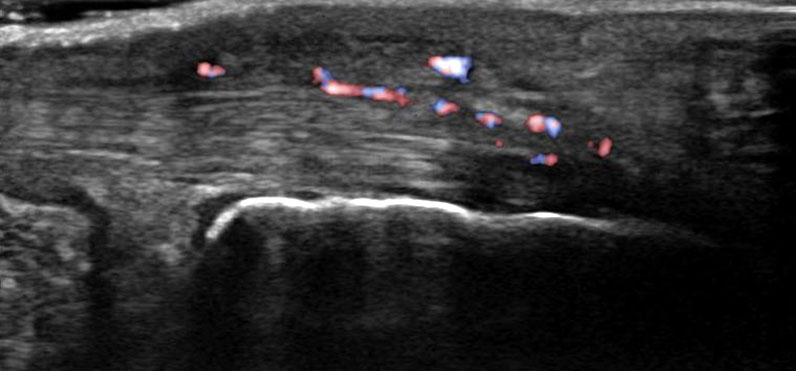

Hier befindet sich ca. 3-5 cm proximal des Tuber calcanei ein als „kritische Zone“ benannter Bezirk, der durch eine ungünstige arterielle Blutzufuhr gekennzeichnet ist (letzte Wiese). Hier finden sich häufig spindelförmige Schwellungen, die bei MRT-Diagnostik nicht selten partielle Nekrosen und Partialrupturen der Achillessehne aufweisen (Abb. 14).

Unabhängig davon können insbesondere chronische Insertionstendinosen der Achillessehne von Partialrupturen (Abb. 15) und erosiven Läsionen des dorsalen Fersenbeines begleitet sein.

Bildgebung

Die sonographische Diagnostik eignet sich primär zur Erkennung schmerzhafter Prozesse im Verlauf der Achillessehne und kann bei Bedarf durch Röntgen bzw. MRT ergänzt werden. Besonders bei längeren Verläufen und kräftigen spindelförmigen Schwellungen (>9mm, Normwert <5mm) im Bereich der kritischen Zone sollte ein MRT zum Ausschluss von Nekrosezonen und Partialrupturen vor Therapiebeginn veranlasst werden. Die sonographisch leicht zu erfassende Veränderung der Sehnendicke im mittleren Sehnenanteil ist ein guter Indikator für die Schwere der Erkrankung und die Beurteilung des Behandlungsverlaufes. Die sichtbaren Veränderungen am distalen knöchernen Ansatz der Sehne sind diskreter.

Insbesondere bei größeren Partialrupturen (Abb. 14) sollten operative Verfahren erörtert werden. Kleinere Partialrupturen sind der ESWT gut zugänglich, wie die beiden nachfolgenden Beispiele zeigen: